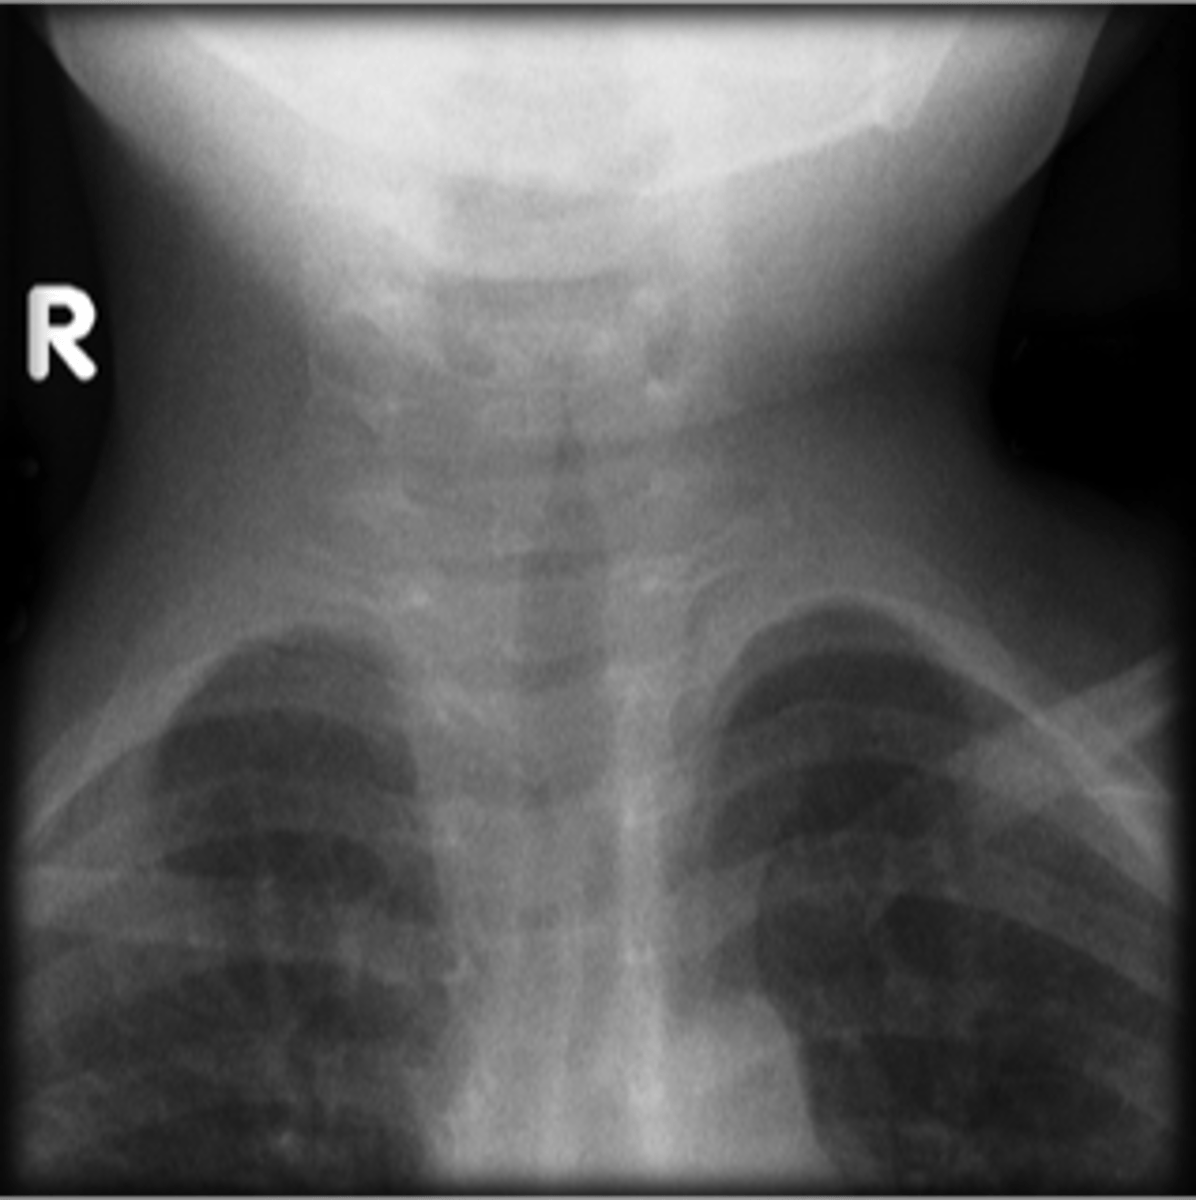

steeple sign (croup)

knowt flashcard image

Croup

Steeple sign- group